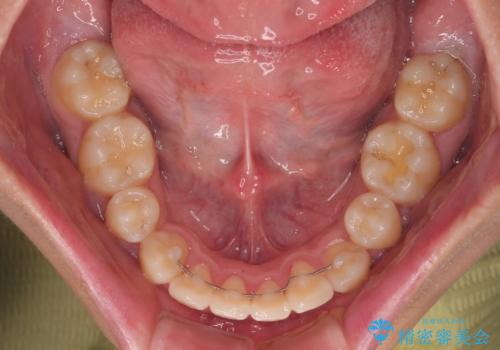

全体的なデコボコをスッキリと ワイヤー装置での抜歯矯正

- 全顎的なデコボコを気にして来院された患者様です。

特に前歯のデコボコが顕著であり、上下左右第一小臼歯の4本を抜歯し、ワイヤー装置を使用して咬み合わせ高さを改善しながら、歯列を整えて行くこととしました。

移動が順調に進み、1年半の短期間で治療を終えることができました。